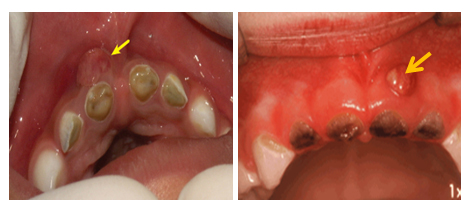

Najnovija istraživanja pokazuju da na našim prostorima 13% (Srbija) do preko 35% (Banja Luka) dvogofišnjaka već ima zubni kvar na tek izniklim mlečnim zubima!? Ova vrsta oboljenja(naziva se karijes ranog detinjstva ili „cirkularni karijes“) veoma brzo napreduje i ukoliko se ništa ne preduzme dovodi do razaranja zuba.(slika 1)

Slika 1. Posledice karijesa ranog detinjstva. Strelicama su označeni otvori gnojnih kanala(fistule) kao znak postojanja procesa u kostima

Ukoliko se razoreni zubi ne uklone predstavljaju stalni izvor infekcije, otežavaju ishranu, ugrožavaju opšte zdravlje i razvoj, ugrožavaju i razvoj stalnih zuba zamenika. Takva deca su neuhranjena,anemična često dobijaju antibiotike što još viće komplikuje varenje i remeti imunitet. Razoreni zubi mogu da remete i razvoj govora. Dokazano je da se kod deca kod koje se pojavio ovaj oblik ranog karijesa mnogo teže sprečava oboljevanje stalnih zuba.